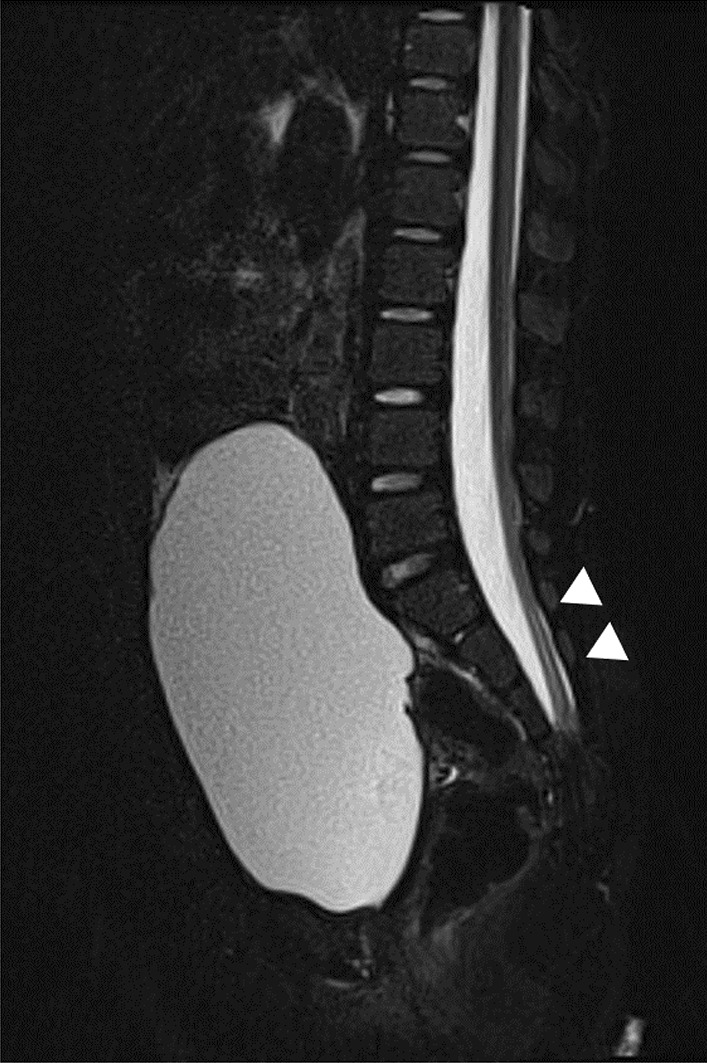

Fig. 1.

Magnetic resonance imaging of the synsacrum during the first visit. Sagittal T2-weighted image showing tethered spinal cord syndrome and syringomyelia (arrowheads)

A 4-year-old Filipino girl was referred to our hospital due to increased frequency of daytime urinary incontinence and foul-smelling urine since the age of 3. She was diagnosed with a lumbosacral myelomeningocele at 21 weeks of pregnancy and born to non-consanguineous parents at 37 weeks of gestation, weighing 2908 g. She underwent myelomeningocele repair 2 days after birth and did not have hydrocephalus. She was able to walk unaided 11 months after birth. Although she had a history of recurrent UTIs, she did not visit a urologist office regularly after surgery. At her first visit to our hospital, her physical and neurological examination was normal, that is, she had a maximum Glasgow Coma Scale score, steady gait, and no paralysis in her legs, and could run as much as other healthy children of the same age. She had a normal bilateral reflex knee jerk and Achilles tendon reflex. Clinical examination revealed constipation and no flexion contractures of her legs. Urinalysis revealed bacteriuria. Magnetic resonance imaging (MRI) revealed a tethered spinal cord (TSC) and syrinx at the S2–3 levels (Fig. 1). A pediatric voiding cystourethrography revealed an enlarged and trabeculated bladder without any vesicoureteral reflux. A urodynamic study (UDS) showed detrusor overactivity and low bladder compliance (1.8 mL/cmH2O). The maximum cystometric bladder capacity was 67 mL, with no specific bladder sensation, and the detrusor leak-point pressure was 77 cmH2O. She was unable to void. She was diagnosed with overflow incontinence (Fig. 2). Clean intermittent catheterization (CIC) was performed and 10 mg of propiverine (0.8 mg/kg body weight/day) was administered orally, and her urinary incontinence resolved. She underwent repeated UDS annually. A UDS at 6 years of age (she had been receiving propiverine for 2 years and 5 months) showed detrusor overactivity and low bladder compliance (3.7 mL/cmH2O), in spite of receiving 10 mg of orally administered propiverine per day. The maximum cystometric bladder capacity was 101 mL, and detrusor leak-point pressure was 50 cmH2O (Fig. 3). She had no urinary incontinence or UTI. However, the cystometrogram showed that her bladder pressure was persistently high. To reduce pressure on the urinary bladder, and avoid the risk of upper urinary tract damage, treatment was switched from propiverine to vibegron, a beta-3 adrenoceptor agonist. After obtaining the patient’s and parental informed consent, a single daily dose of 25 mg of vibegron (Beova; Kissei Pharmaceutical Co., Ltd., Tokyo, Japan) (1.4 mg/kg/day) was administered. After 5 weeks of once-daily vibegron treatment, UDS was performed and showed disappearance of detrusor overactivity, increased maximum cystometric bladder capacity (251 mL), and improved bladder compliance (9.0 mL/cmH2O) (Fig. 4). She has continued to receive vibegron that has been well tolerated and to perform CIC for 7 months so far, and no UTI, incontinence, or drug-related adverse events have been observed. No abnormalities were found in blood pressure (98/60 mmHg) or heart rate (72 beats/min) or on the blood tests after a month of receiving vibegron. Her detailed laboratory data (before and after taking vibegron) are presented in Table 1.